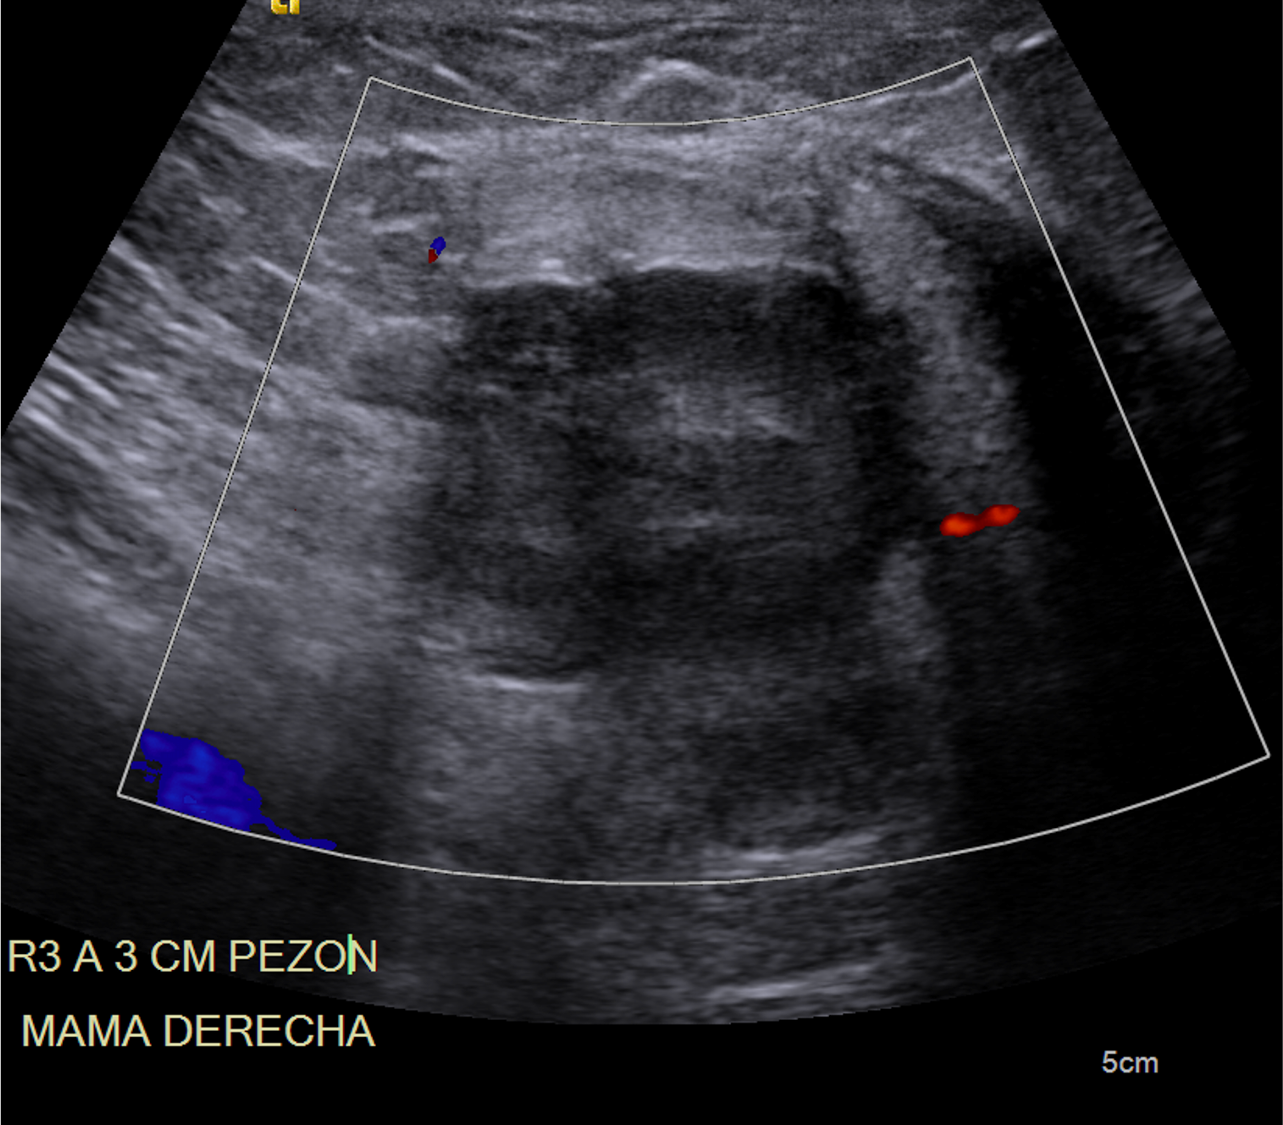

Imágenes de ecografía mamaria derecha con tranductor lineal (A, B, C), y a nivel subclavio derecho (D) y en región axilar derecha (E).

F. Mama derecha heterogénea, por la presencia de nódulo de composición sólida, homogénea, con realce periférico tras la administración de medio de contraste, localizado hacia cuadrantes internos y medidas aproximadas de 28×41 mm.